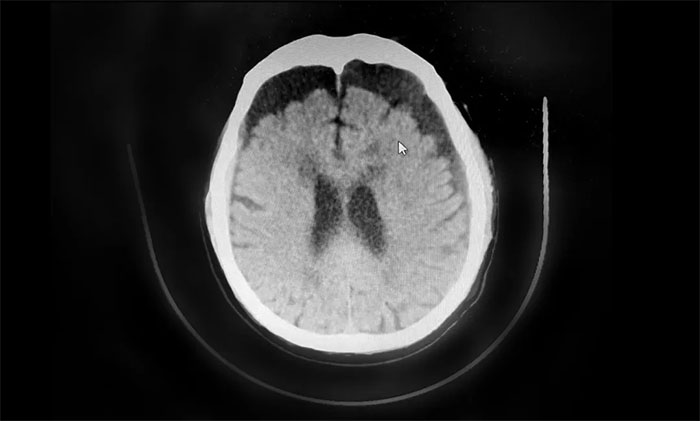

▲ 术后复查,血肿得到明显改善

待病情稳定并评估后,近期,于耀宇主任又为患者开展了双侧“硬脑膜下钻孔引流术”,促使硬膜下积存的大量血肿快速排出,解除脑组织压迫,缓解头晕、肢体乏力等症状。术后,患者健康状况平稳,病情正逐渐好转。